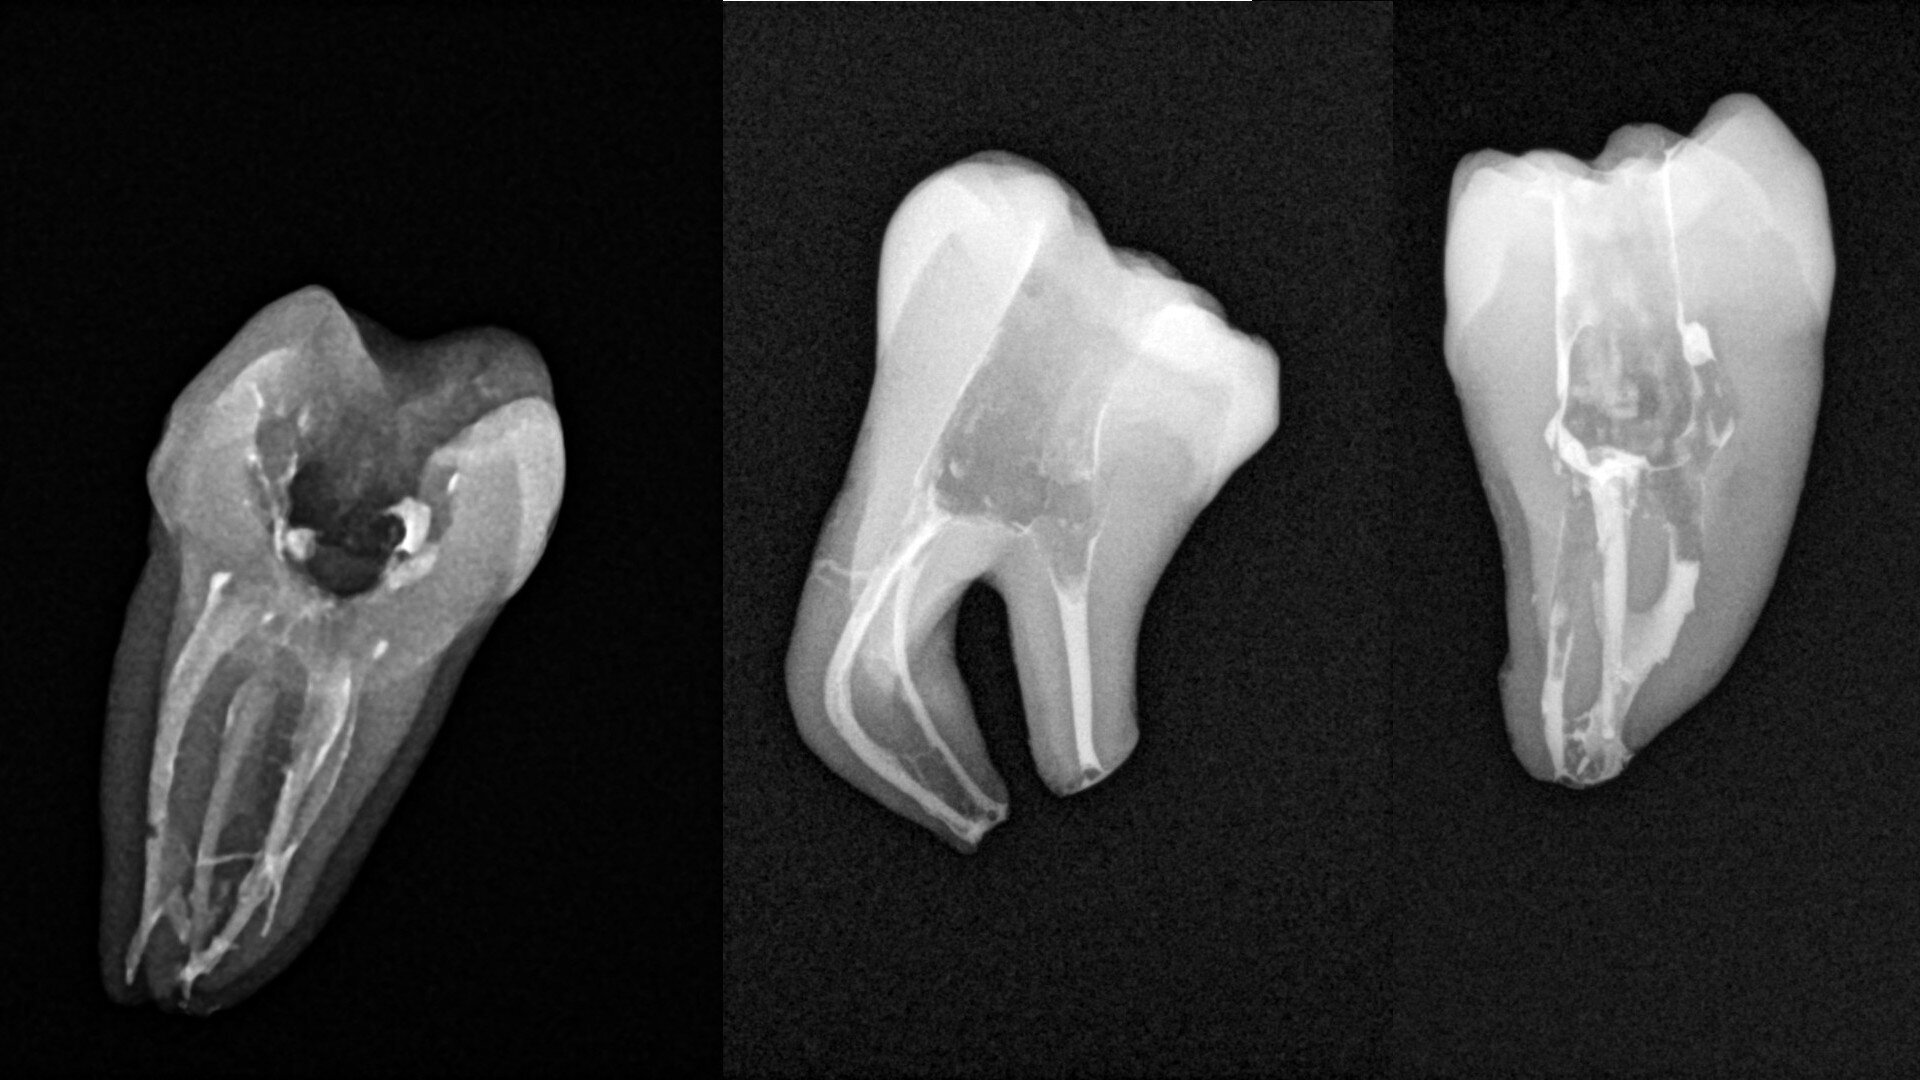

Micro-CT scans allowed clinicians to improve their knowledge about the complexity of the root canal system. This kind of image can help the clinician to understand the network of blood vessels inside the roots, especially in the molars. Comparison of micro-CT scans with radiographs available on the internet reveals that there is a visible difference between the micro-CT scans and the postoperative radiographs regarding the quality of obturation. The most visible difference is in the area of the apical delta and isthmuses between the canals. This difference led us to deduce that, even though root canal therapy procedures are very successful, a great deal of root canal space is not cleaned of hard-tissue debris and filled with obturation material.

The first trials of the LPE concept were performed on extracted human molars. Although the dynamics of fluid during root canal irrigation are completely different in vivo than in extracted teeth, these kinds of trials provide initial information about the procedure. Some of these teeth had apices closed with a coat of wax and composite resin to close the apical delta and simulate the periapical tissue. After creation of the access cavity, the pulp chamber was cleaned with continuous irrigation with 5.25% NaClO activated with a SkyPulse laser (Fotona) in AutoSWEEPS mode (20 Hz, 15 mJ). A 25/0.07 reciprocating file (Shenzhen Perfect Medical Instruments) was used to perform the pre-flaring procedure. After opening the coronal third, continuous irrigation with 5.25% NaClO activated with the laser was used to clear the debris for 30 seconds. After removing the debris, a #10 C-PILOT file (VDW) was used to establish apical patency, without forcing the file if possible. In some cases, apical patency was reached already at this stage of root canal preparation. In all cases, the second step of instrumentation was the preparation of the middle third with the same file, and the same irrigation procedure was performed. Subsequently, the C-PILOT file was used to reach the apical foramen. At this stage, apical patency was reached in most cases, but in some roots, there was no possibility of entering the apical foramen. The working length was confirmed with a radiograph with the hand file. Usually, the next procedure to be done is apical preparation, but the LPE concept is based on an enhanced irrigation protocol. Following this protocol, irrigation was performed for 5 minutes with continuous flow of 5.25% NaClO activated with the SkyPulse laser in AutoSWEEPS mode (20 Hz, 20 mJ) with a conical sapphire fibre. The next step was alternating irrigation with 17% EDTA for 30 seconds, with 5.25% NaClO for 30 seconds and with 17% EDTA for 30 seconds, all activated with AutoSWEEPS, followed by irrigation for another 5 minutes with 5.25% NaClO activated with AutoSWEEPS. In most cases, the next step after this stage of enhanced irrigation was the calibration of the apical constriction rather than apical preparation per se, but this step requires further investigation.

The in vitro trials and in vivo cases, periapical radiographs and postoperative CBCT images demonstrate that the laser activation of irrigants allows the clinician to achieve much better removal of the hard-tissue debris than with the conventional irrigation methods. The LPE concept appears promising in terms of the improved removal of hard-tissue debris. It is important to mention that this is only a clinical observation. The most important part of this observation is a very rapid flow of the irrigants between the root canals located in the same root after the LPE enhanced irrigation protocol with the SkyPulse laser but before apical preparation.